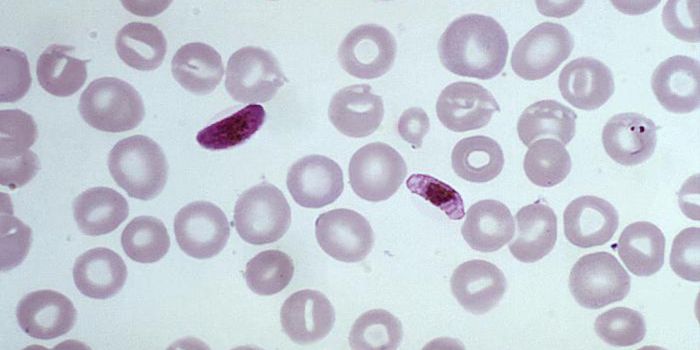

NOV 23, 2021MicrobiologyWhen the parasite Plasmodium falciparium is transmitted from mosquitoes to humans, it causes malaria. So what does it do ...

NOV 05, 2021MicrobiologyMalaria is the most common infectious disease in the world, and infected over 225 million people in 2019 according to th ...

FEB 04, 2021ImmunologyMalaria is a disease caused by single-celled parasites from the Plasmodium group, transmitted to humans through infected ...